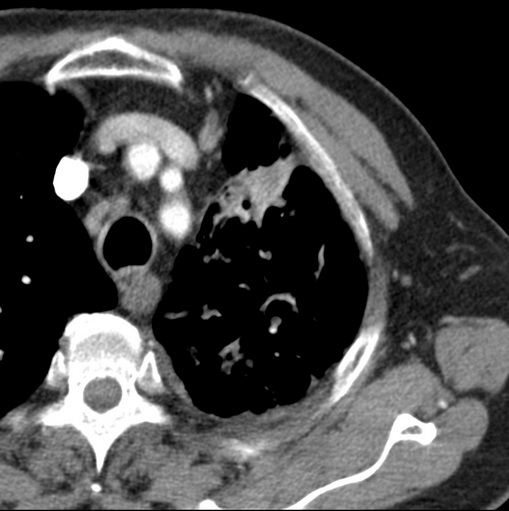

男性患者 81岁 咳嗽 咳痰 咯血

肿块贴近左肺门,包绕左上肺动脉,形态不规则。肿块增强扫描中度强化。纵膈内主动脉弓左旁间隙、气管隆突前、下间隙见多枚淋巴结影。综上考虑左侧中央型肺癌可能性大。图片没有完整上传,尤其是左肺上叶支气管分支层面没有上传,因此不好判断是叶支气管中断还是段支气管中断。另外,下图红色部分所示是“黏液支气管征”吗?